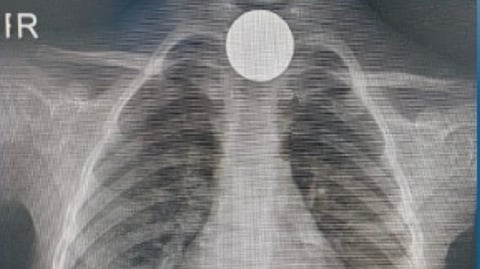

وأظهرت الفحوصات الطبية أن الجسم الغريب عبارة عن عملة معدنية من فئة الريالين، وكانت مستقرة في القسم العلوي من المريء.